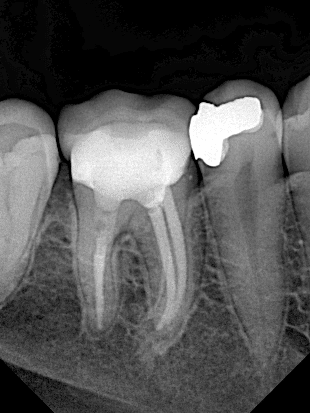

27 years old patient come to clinic asking to restor her lower first molar , she did the filling more than 10 years ago , the treatment was just remove the old amalgam and screw and fill the screw space with( daul cure material or bioceramic putty and sealer or MTA .. ) here I use the dual cure material to fill the space after special treatment and restor the crown with indirect lithium disilicate overlay

Initial situation , 10 years ago the patien did this endodontic treatment and amalgam filling

Pre-operative x ray showing the large defective amalgam and screw